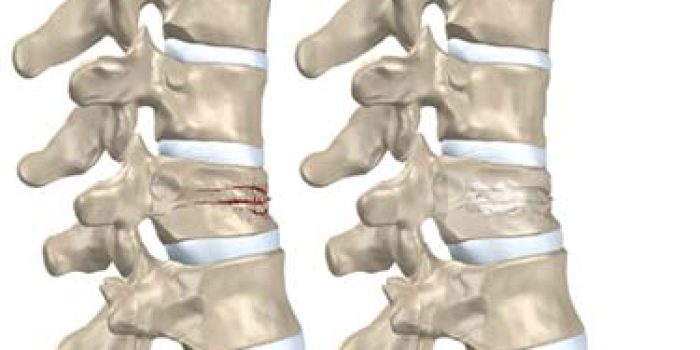

ساییدگی ستون فقرات یا اسپوندیلوز یک وضعیت شایع است که مرتبط با تغییرات در ستون فقرات و مهرهها است. در واقع، این تغییرات ساییدگی از سن تقریبی ۲۵ سالگی آغاز میشود و تا سنوات میانه تقریباً در تمام افراد مشاهده میشود. کمر انسان بار زیادی را در قالب وزن بدن و همچنین اشیاءی که بلند میکنیم تحمل میکند و همواره در حال خم شدن و چرخش است به همین دلیل تغییرات آرتروز ستون فقرات بیشتر در ناحیه مهره های کمری دیده می شود که اصطلاحا به آن اسپوندیلوز کمری گفته میشود. اسپوندیلوز کمری بیشتر در مهره های پایینی کمر، بخصوص در بین مهره های چهارم و پنجم کمر (L4/l5) و بین مهره پنجم و قسمت اول استخوان خاجی(دیسک بین مهره ای L5-S1) رخ می دهد و منجر به درد سیاتیکی میگردد. فرسایش معمولاً در دیسکهای بین مهرهای رخ میدهد. این عارضه به طور متمایز از آرتروز است که قبلاً اشاره شد. فرسایش دیسک، به عبارتی خود فرسایش دیسک کمر، عاملی برای آرتروز ستون فقرات است. به این دلیل که دیسکهای فرسوده قدرت جذب ضربه را از دست میدهند و نمیتوانند مانع از سایش و فرسایش مفصلهای ستون فقرات شوند.